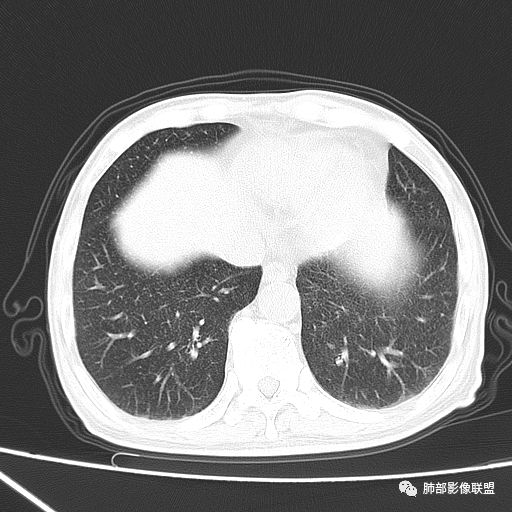

2019年9月12日CT(外院片,手机拍摄)

2019-10-20复查CT如下:

两肺弥漫性粟粒样结节伴左上肺小结节,呈三均匀分布,有结核的临床表现,支持血性播散性肺结核。

大小、分布均匀,边缘清楚

细小结节,弥漫,撒米粒样——血道来源

部分可见分支状

边缘稍平直

毛刺细弱

还是支持结核

血道来源的病灶,均匀、细微,而且部分有分支状,都符合粟粒型肺结核

急性血行播散型肺结核  两肺广泛分布粟粒大小的结节状密度增高影,具有大小均匀、分布均匀、密度均匀的典型“三均匀”特征,注意急性血播病灶非常小,一般粟粒影直径1~2mm。

病灶密集者出现肺外围血管影不清或减少。

发热初期肺部可缺乏典型影像学改变,1到2周后出现的广泛粟粒结节对诊断具有高度提示作用!